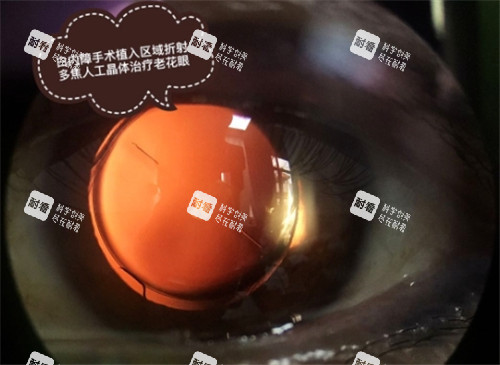

人工晶体是植入眼内、替代原有浑浊晶状体的关键部件,其功能、材质、设计的不同,直接导致了价格的巨大差异。

从基础的改善视力,到同时解决近视、远视、散光甚至老花眼问题,不同功能的晶体满足了患者不同的视觉质量需求。

高端档多功能晶体:这是目前技术头部的代表,旨在实现真正的“屈光性白内障手术”。

主要包括多焦点晶体、三焦点晶体、景深延长型晶体等。

它们的设计原理复杂,能够同时提供远、中、近多个距离的清晰视力,极大程度帮助患者摆脱术后对老花镜或近视镜的依赖。